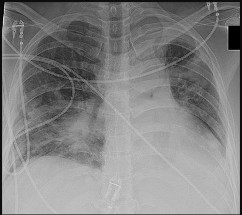

Figures 5a and 5b are the radiographs of a 74-year-old man with poorly differentiated squamous cell carcinoma of the lung. He has had an uneventful recovery after undergoing a wedge resection of his left upper lobe 6 months ago. He is experiencing left lateral knee pain, and a whole-body positron emission tomography/CT scan shows no avid area other than the lateral left distal femur. This patient has needed to use a wheelchair for 3 weeks because of his pain. You discuss these treatment options: aggressive curettage, local adjuvant treatment, cementation, and prophylactic fixation vs distal femoral resection and megaprosthesis total knee arthroplasty reconstruction. You should tell him that

Distal femoral megaprosthetic reconstruction after tumor resection is a reliable oncologic procedure, but 5-year implant survival is as low as 74% with an approximate 8% deep infection rate. The amputation rate is as high as 8% because of infection or recurrence, and there is an overall 18% revision rate. More than 10% of distal femoral megaprosthetic reconstructions are performed to address metastatic disease.

Fixation failure and infection may occur with either procedure. Radiation may not be recommended after a megaprosthesis reconstruction unless margins are not free of tumor. Either operation may be equally successful in returning patients to functional activities. Overall disease-free survival is related to the aggressiveness of the tumor and not the type of reconstruction performed.